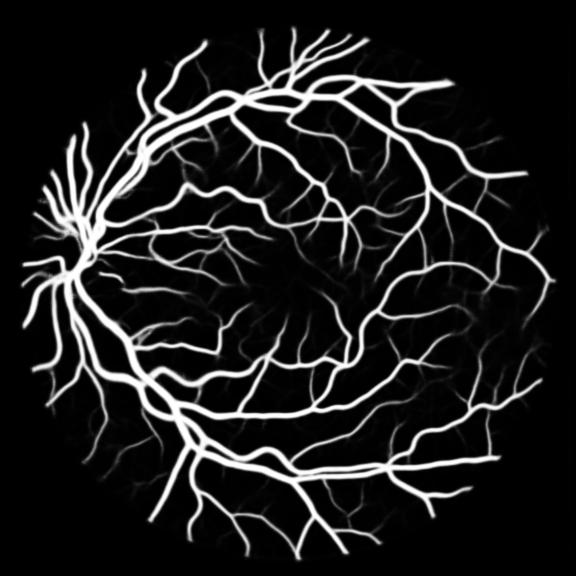

All three datasets are processed by subtracting the mean and normalizing according to the standard deviation. We use Adam optimizer, set the initial learning rate to 0.001 which is reduced by ten times if the training set loss does not drop during 10 consecutive epochs. We augment data using rotation, crop, flip, shift, change in contrast, brightness and hue. We set batch size to 4 for Skin Dataset and 32 for DRIVE and CHASE_DB1 whose patch size is relatively smaller. For each model we train 50 epochs and the result is shown in Table 1. Models with MixModule have better performance than those not and the best performance in each metric all comes from MixModule-based models. We also show some outputs of the networks in Figure 4.